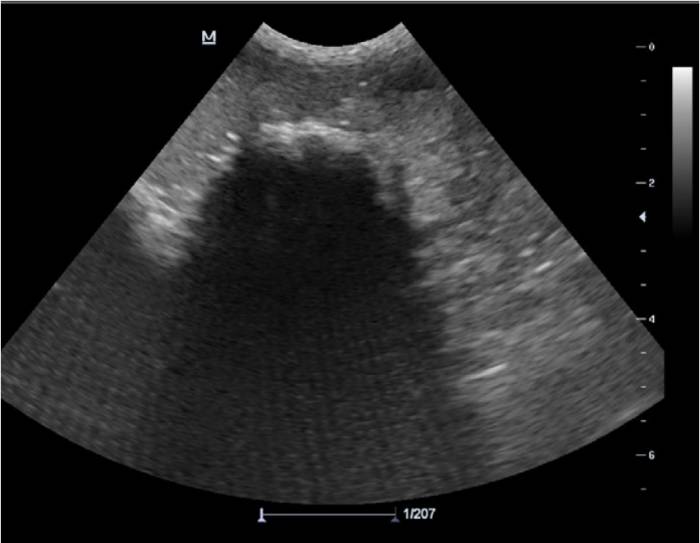

Рис. 1. УЗИ. Инородное тело желудка – причина хронической рвоты.

Хроническая рвота может быть единственным симптомом различных заболеваний. Поэтому сначала необходимо исключить системные болезни, не относящиеся к ЖКТ, а также наличие инородных тел и объемных новообразований с помощью визуальной и лабораторной диагностики. Рвоту часто связывают с поражением желудка, но воспаление тонкого и толстого кишечника и алиментарная лимфома могут проявляться только хронической рвотой без диареи.